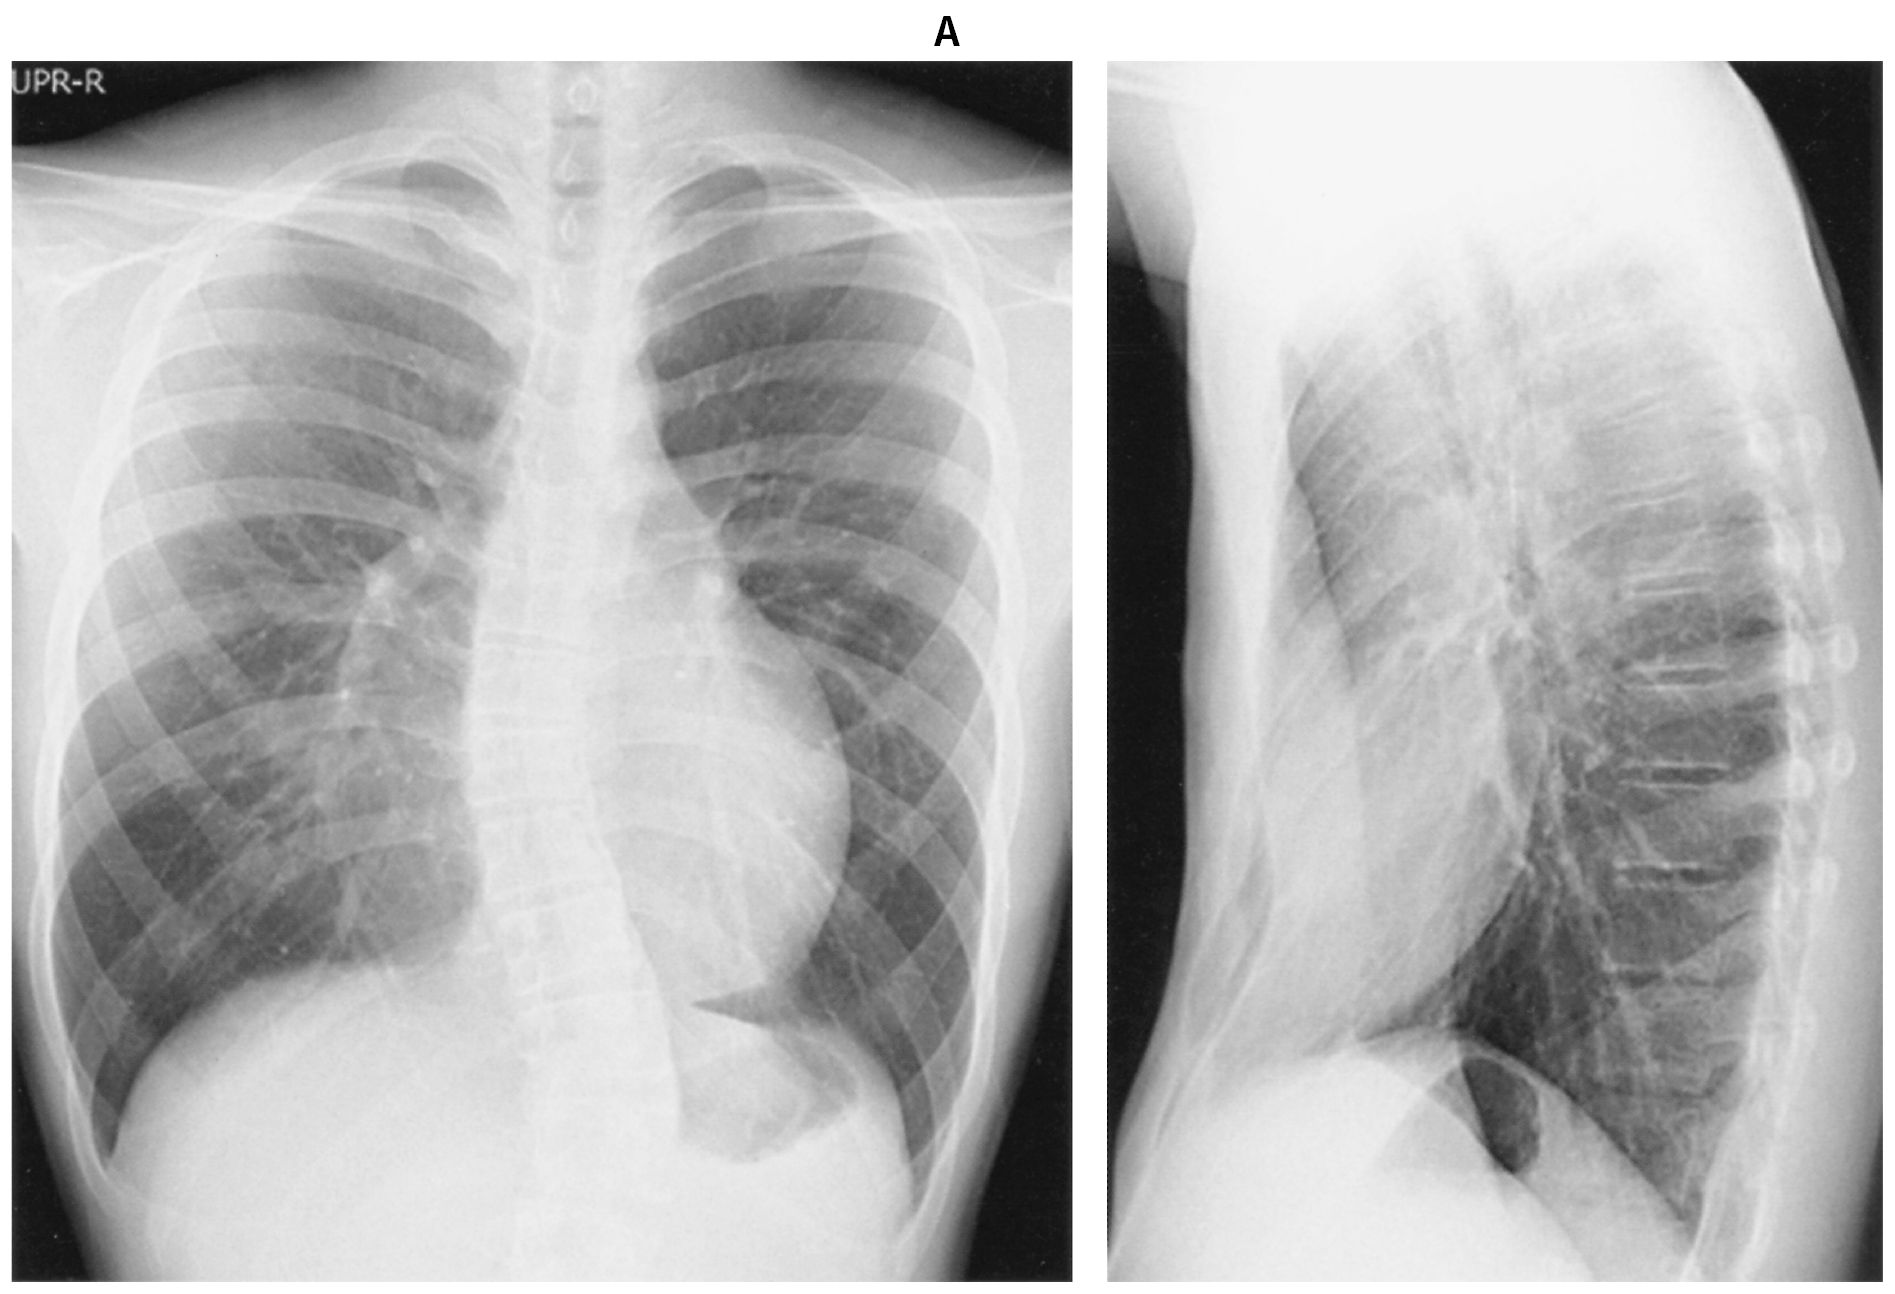

12歳の男児。胸郭の変形を主訴に来院した。学校で着替えの際に友人に胸の形について指摘され,本人が気にしている。自覚症状はない。意識は清明。身長158cm,体重40kg。体温36.6℃。脈拍60/分,整。血圧122/76mmHg。SpO2 96%(room air)。胸部エックス線写真(A)と胸部単純CT(B)とを下に示す。